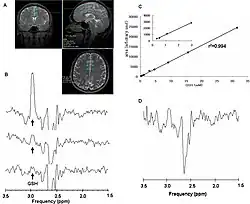

Bildgebende Verfahren

Mit Hilfe der bildgebenden Verfahren ist eine nichtinvasive Darstellung und Messung der Durchlässigkeit der Blut-Hirn-Schranke mit verschiedenen Substanzen möglich. Diese Verfahren werden zum Teil in der klinischen Praxis in der Humanmedizin angewendet. Zur Anwendung kommen dabei die Positronen-Emissions-Tomographie (PET), die Magnetresonanzspektroskopie (MRS) und die Magnetresonanztomographie (MRT).

- Magnetresonanzspektroskopie

Die Magnetresonanzspektroskopie (MRS) ist ein auf der Kernspinresonanz basierendes Verfahren, das in einem Magnetresonanztomographen die Durchführung einer Kernspinresonanzspektroskopie ermöglicht. Dabei können bestimmte Substanzen, beziehungsweise deren Stoffwechselprodukte, im Gehirn spektroskopisch nachgewiesen und quantifiziert werden. Gegenüber der auf dem Protonenspin des Wassers basierenden Magnetresonanztomographie sind hier andere Atomkerne von Interesse. Dies sind insbesondere 19F, 13C, 31P und nichtwässrige Protonen. Im Vergleich zu den in wesentlich größeren Mengen vorhandenen Protonen des Wassers liefern diese meist nur in Spuren vorhandenen Kerne entsprechend schwache Signale. Die räumliche Auflösung entspricht einem Volumenelement von ungefähr 1 cm³. MRS und MRT lassen sich leicht miteinander kombinieren. Die MRT liefert dabei die anatomische Struktur und die MRS die entsprechende räumlich aufgelöste Analytik zur Anatomie. Mit der MRS lässt sich beispielsweise die Pharmakokinetik Fluor-haltiger Wirkstoffe, wie der Neuroleptika Trifluoperazin und Fluphenazin, im Gehirn eines Menschen beobachten und messen.[200] Dabei lässt sich mit der Magnetresonanzspektroskopie quantitativ zwischen dem Wirkstoff und seinen Metaboliten unterscheiden. Ebenso kann zwischen freiem und gebundenem Wirkstoff differenziert werden.[201][202]

Nachteilig bei der MRS sind die durch die geringe Empfindlichkeit der Methode notwendigen langen Messzeiten und die geringe räumliche Auflösung. Letztere ist insbesondere bei Kleintierversuchen problematisch.[189]